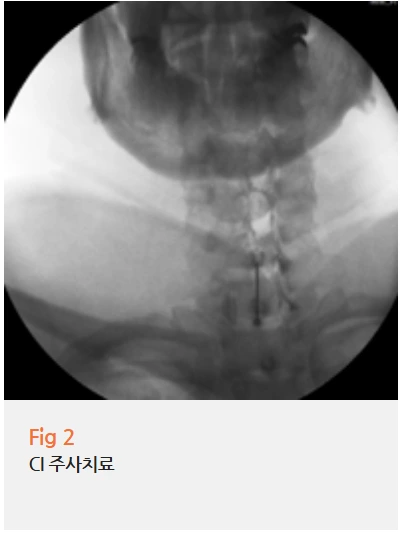

CI 주사치료, 그리고 달라진 일상

진단이 명확해지면 치료 방향도 명확해져요.

저는 환자분께 CI, 즉 C-arm Intervention 주사치료를 권유드렸어요.

C-arm이라는 영상 장비로 실시간으로 확인하면서 정확한 신경 경로에 약물을 주입하는 방식입니다.

단순히 겨드랑이 주변 근육에 주사를 놓는 것과는 전혀 다른 접근입니다.

정확하게 눌린 신경 부위를 타겟으로 해야 효과가 있어요.

실제로 시술 후 환자분은 한 달 넘게 이어지던 왼쪽 겨드랑이 밑 통증이 눈에 띄게 줄어들었다고 하셨어요.

이후 남아 있던 등 통증과 팔 저림도 추가적인 주사치료를 거치면서 함께 호전됐어요.